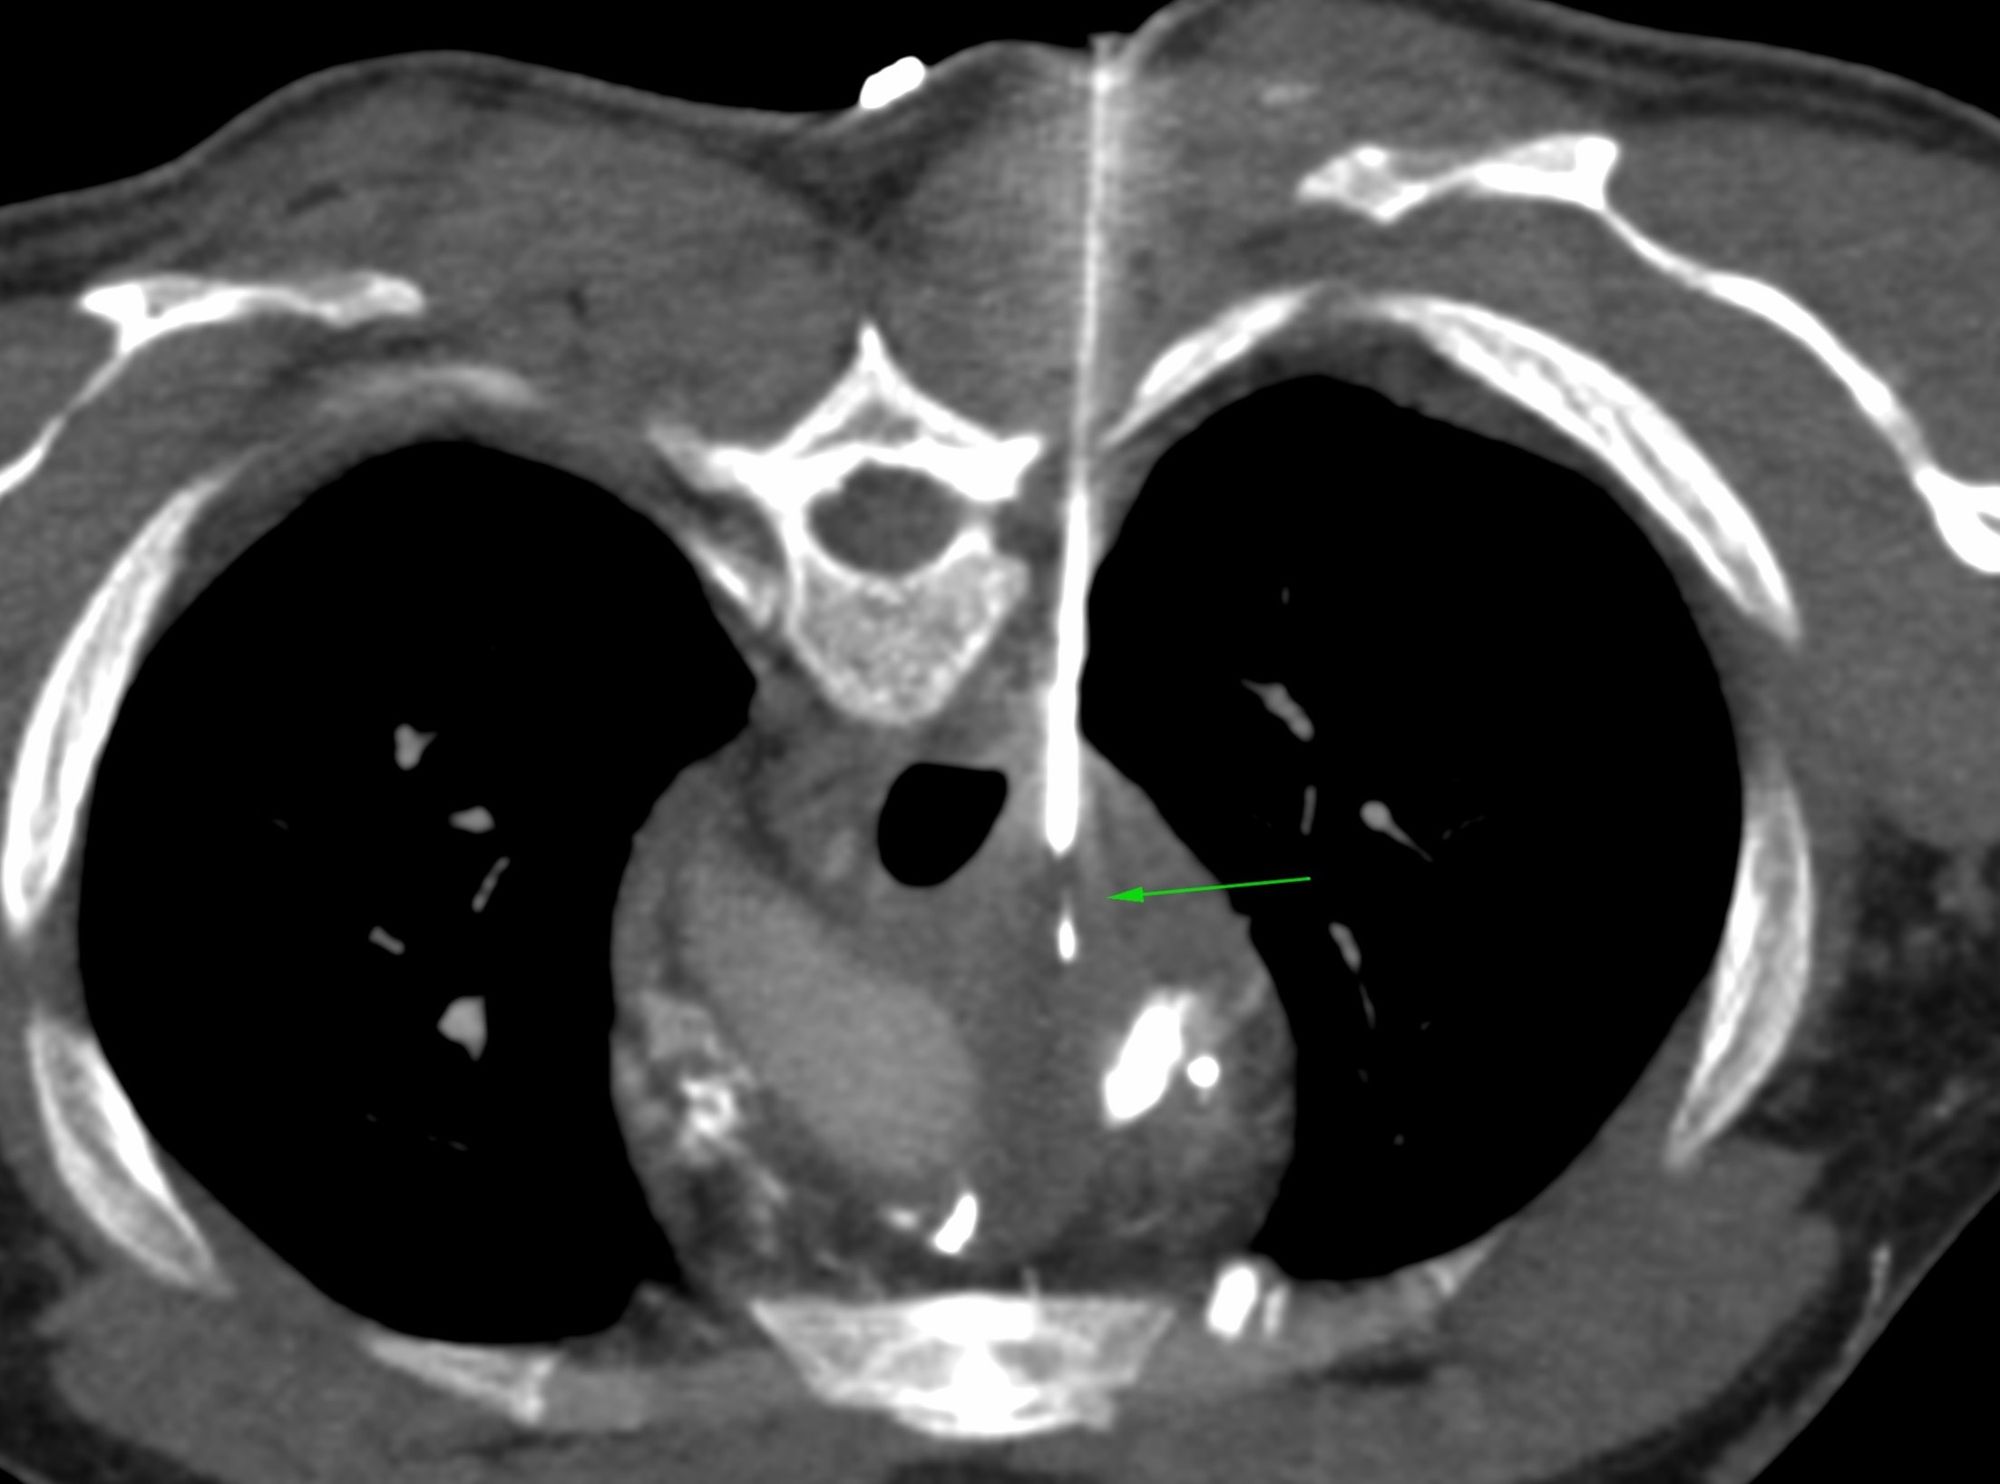

Case 31: Subcarinal Node Biopsy - Transpulmonary Approach

Bhavin Jankharia - 10 May 2021